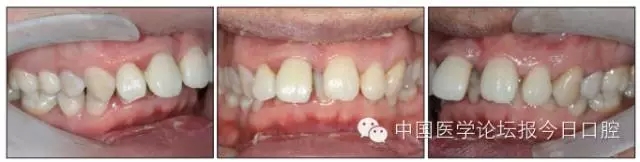

14.webp.jpg

15.webp.jpg

圖9 治療后口內像